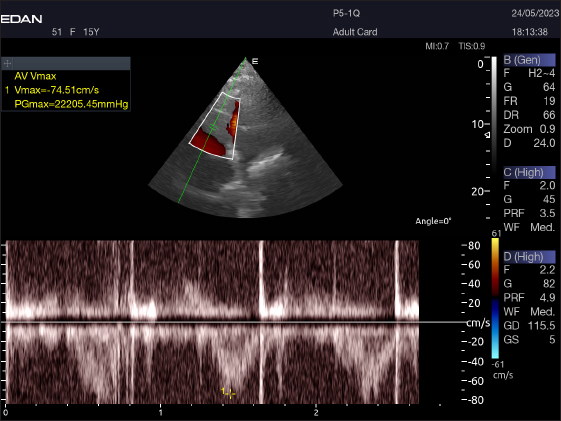

Table 4 provides an overview of pulsed-wave Doppler echocardiographic serial measures in adult racing camels. The pulsed-wave Doppler echocardiographic measurements’ mean values ± standard deviation were recorded for Tv E/A (1.3 ± 0.2 cm2), Mv E/A (1.3 ± 0.2 cm2), Av max (−88.2 ± 25.1 cm/second), and Pv max (−59.2467 ± 17.4 cm/second), as shown in Table 4.

The Mv E/A (Fig. 8), Tv E/A (Fig. 9), and maximum velocity of the aortic valve (Av Vmax) (Fig. 10) were all measured using pulsed-wave Doppler at LPSLAx in all camels. Two cases were observed with mild mitral regurgitation detected through continuous-wave Doppler, but the regurgitation was not considered significant (Fig. 11).

Fig. 10. Normal flow of the aortic valve is demonstrated by left caudal–parasternal spectral PWD Doppler in a 20 years old camel.